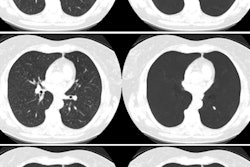

Not surprisingly, AI was the top trend at the recent European Congress of Radiology (ECR) in Vienna. Click here for our report. You can also learn about how AI can help distinguish lung nodules on CT scans and how it can detect intracranial calcifications.